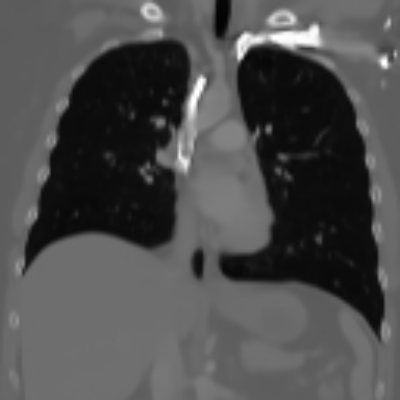

| Real-style X-rays | X2CTGAN | PerX2CT | DX2CT | ||

| PA | ![]() |

Coronal | ![]() |

![]() |

| Lateral | ![]() |

Sagittal | ![]() |

| Axial | ![]() |

The qualitative results in Figure 4 with real-world biplanar X-rays show that the structure of organs in reconstructed CTs by DX2CT better resembles to that of X-rays and DX2CT reconstructs sharper results, compared to the SOTA methods.